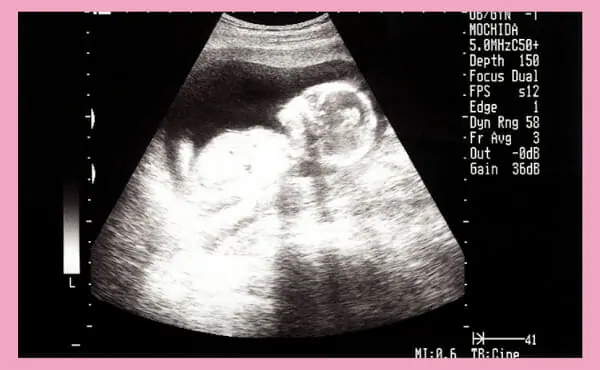

妊娠15週目のエコー写真です。

妊娠15週のエコー検査でわかること

妊婦健診によるエコー検査は妊娠4〜11週は経膣エコーとなり、12週からはお腹の上から超音波で検査をおこなう腹部エコーとなります。

妊娠15週の時期には赤ちゃんの外性器も形成され、エコー検査では赤ちゃんの身体の向きによって、性別が判断できることも少なくありません。なお、医療機関によってはエコー検査による性別の判断結果を教えてもらえないことがあるため、事前に確認すると良いでしょう。